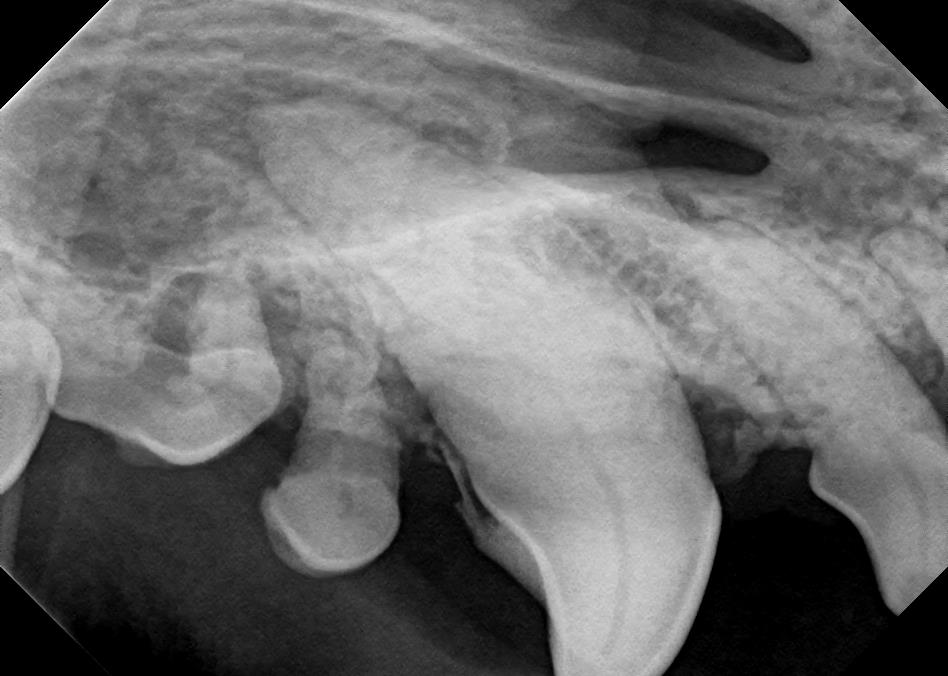

Examples of healthy teeth:

At A Couple of Vets, our animal hospital staff is well-versed in the latest dental cleaning techniques to remove plaque and tarter from the teeth’s surface as well as from below the gum line. We perform dental x-rays at every cleaning to ensure that the teeth are completely healthy. They may look good on the surface, but many problems occur below the gum line and are only visible with x-rays.